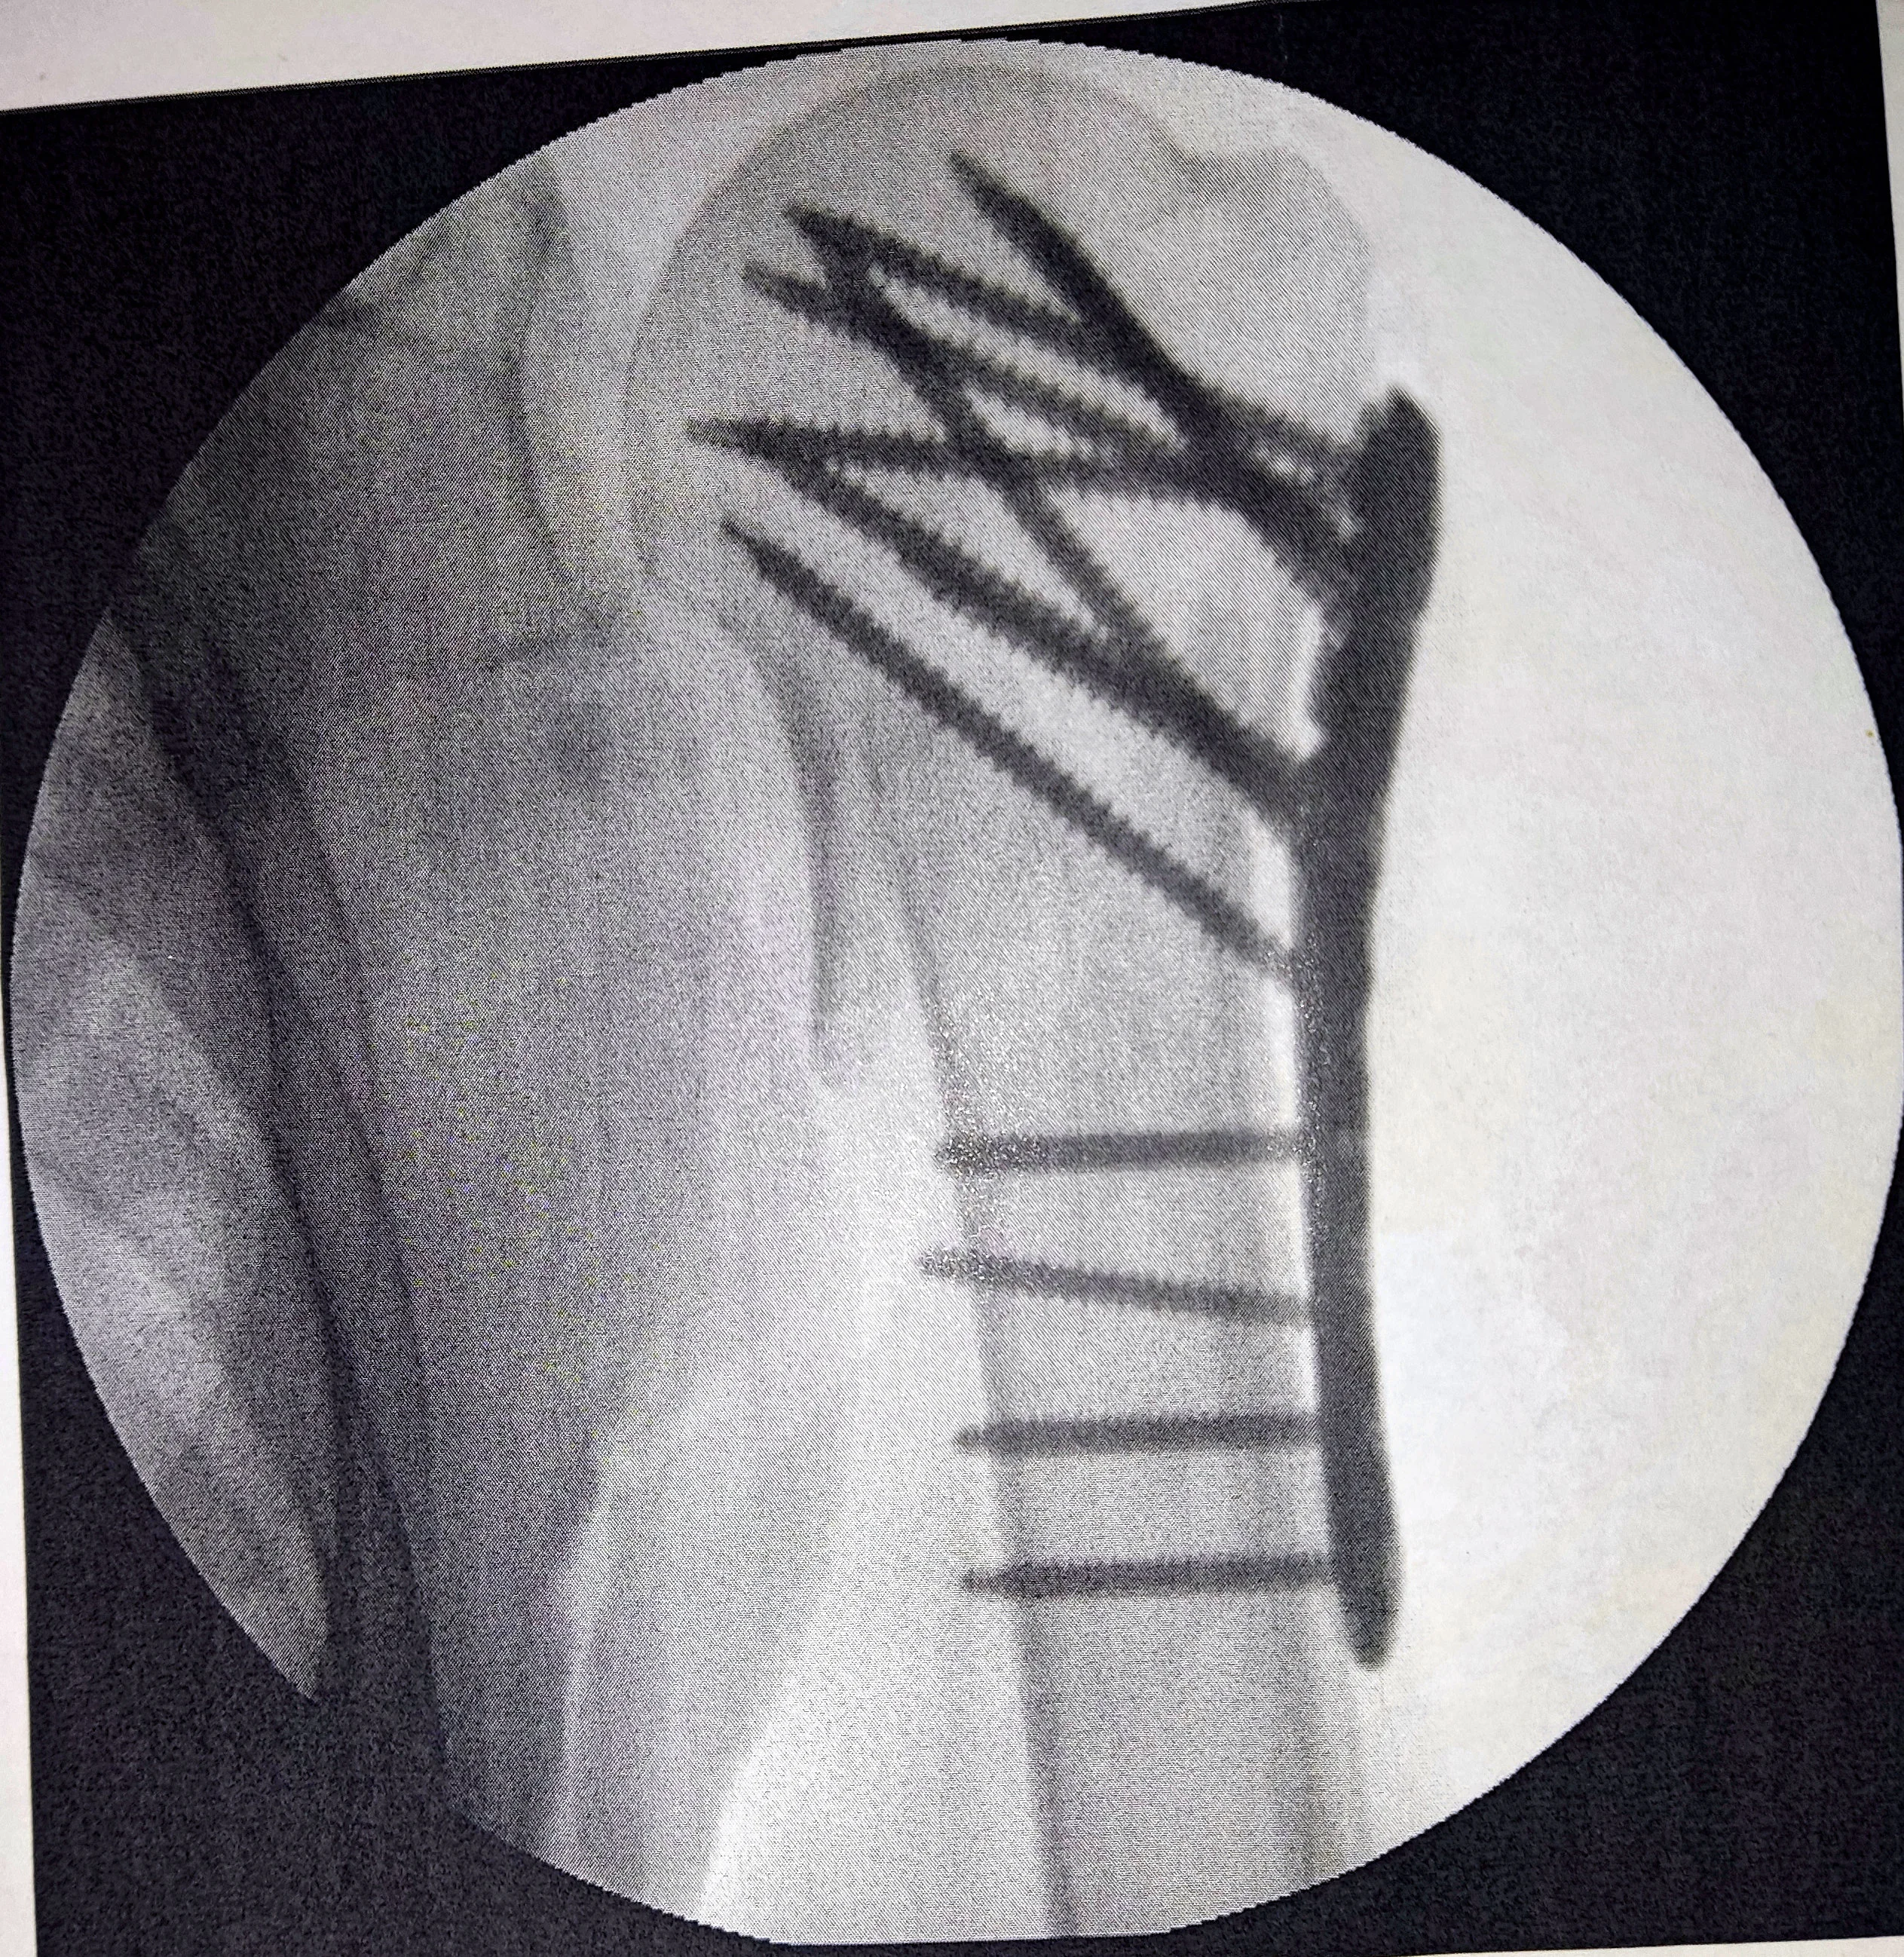

Am 7. April wurde ich operiert. Nun bin ich wieder zu Hause. Der Knochen wurde nicht genagelt, sondern mit einer Platte und Schrauben versorgt.

Hier auf dem Röntgenbild kann man die Platte und die Schrauben gut sehen.

Der Unterarm sieht im Moment noch aus wie ein Luftballon, an dem ein paar kleine Fingerchen hängen, und alles ist blaubraun bis schwarz, der platzt bald. Da, wo die Platte ist und wo der Bruch war, sieht man aber keine Schwellung. Dieser Schulter-/Oberarmbereich ist allerdings auch noch verbunden, so dass man dort sowieso nicht viel sieht, und wahrscheinlich hat sich dort durch den Druck des Verbandes eine beginnende Schwellung nach unten verlagert. Am Unterarm habe ich ja keine Verletzung, deshalb ist die massive Schwellung dort für mich komisch, aber so etwas kann nach einem Bruch oder einer Operation wohl auch weiter unten auftreten, also egal. Das geht hoffentlich auch bald wieder weg. Schmerzen habe ich natürlich noch. Dagegen nehme ich Tilidin und Metamizol. Im Moment kann ich noch nichts machen, und wenn ich was mache, verursacht das starke Schmerzen. Ich soll den Arm noch schonen und nicht versuchen, ihn zu bewegen. Jetzt kann ich aber wieder schlafen. Ansonsten war es das dann auch gewesen. Jetzt muss ich nur noch genesen und in 14 Tagen die Fäden ziehen lassen, alles andere ist getan. In 6 Wochen ist das Ganze Geschichte, glaube ich.